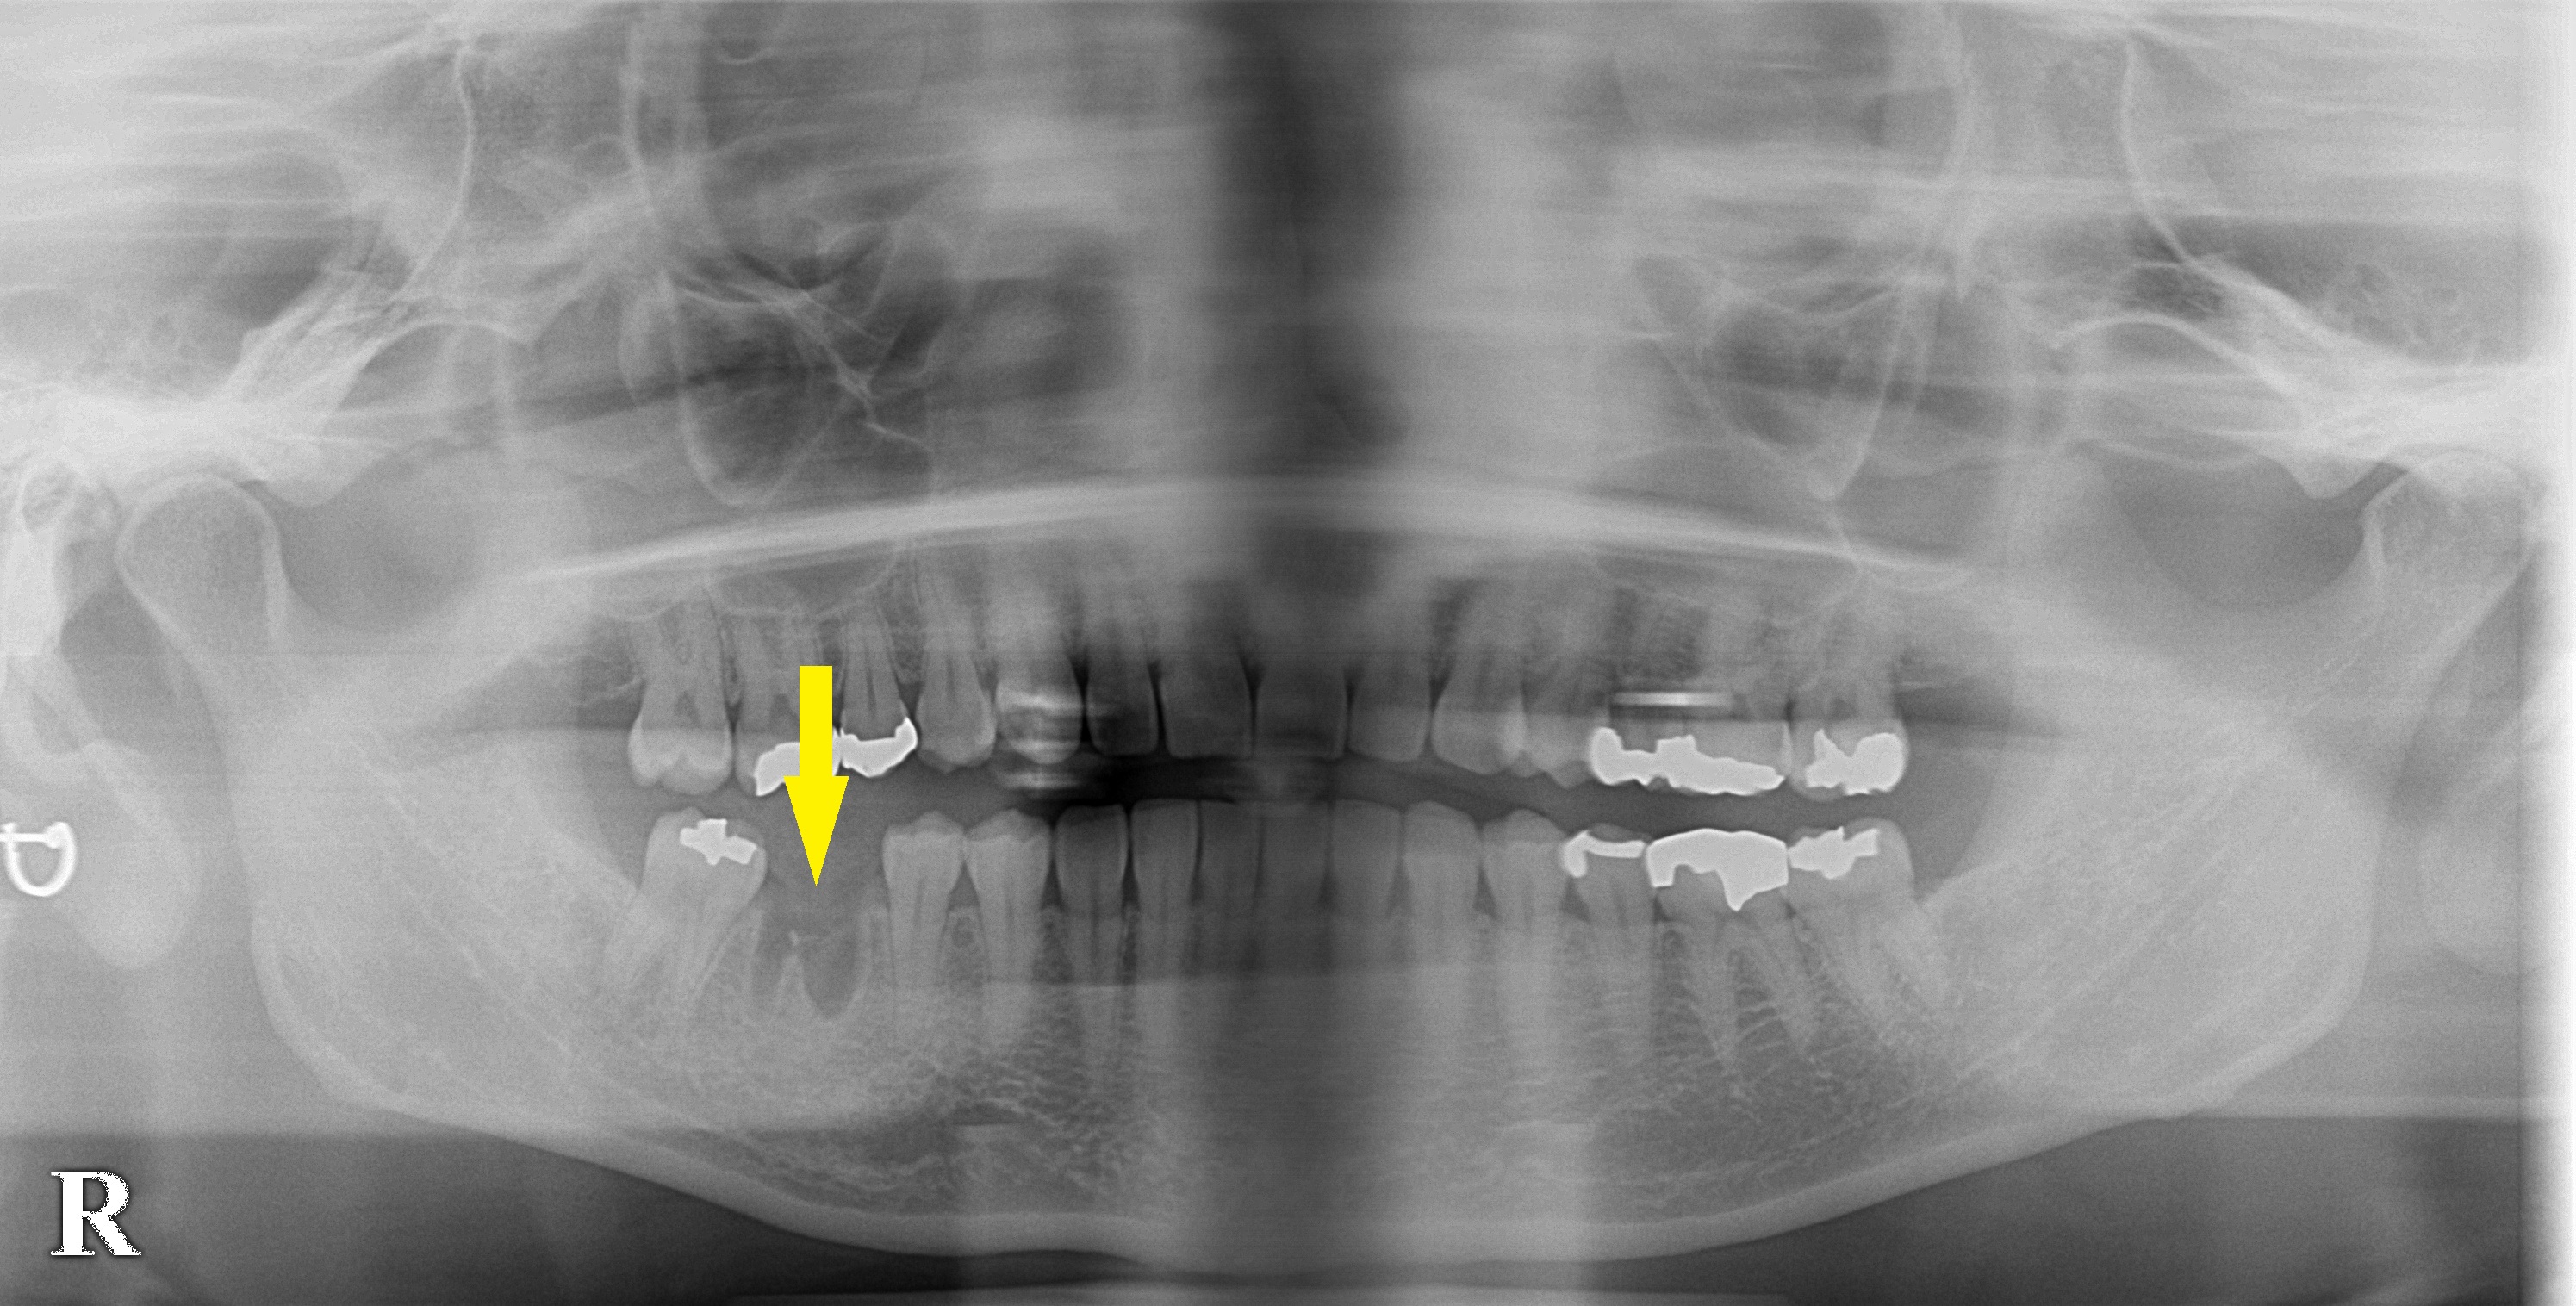

即時埋入の機会を外したら、待機手術で 今週のインプラント症例 2020.07.102026.01.19 患者様は名古屋在住の40代女性。 右下顎第一大臼歯の歯根の状態が悪く、何度も歯根の治療を繰り返していたそうですが、結局は抜歯となってしまったそうです。 同部のインプラント治療を希望されて来院されました。 抜歯してから1か月ほどだったので、レントゲン写真では、まだ抜いた歯根の穴が残っているような状態でした。 4か月ほど待機して、抜いたところに骨が少し回復してくるのを待ち、本日インプラント埋入術を行いました。 症例・コラム一覧に戻る